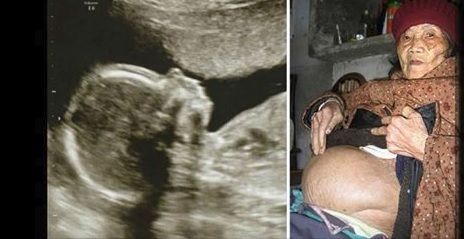

Caz bizar in China. O femeie in varsta de 92 de ani si-a petrecut ultimii 60 de ani insarcinata. Femeia a ajuns la medici acuzand dureri groaznice de abdomen, iar specialistii au ramas uluiti cand au descoperit cauza.

Potrivit DailyMail, femeia a trait peset jumatate de secol cu un fat nedezvoltat in uter.

In scurt timp, medicii au descoperit si motivul pentru care femeia a stat atat de multi ani cu fatul mort in uter. Se pare ca batrana refuzase in tinerete sa se supuna operatiei prin care ar fi trebuit sa fie indepartat fatul, pe motiv ca nu dispunea de o situatie financiara foarte buna si a preferat sa traiasca astfel pana la sfarsitul vietii.